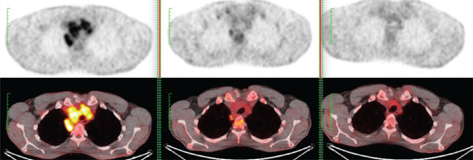

In 2009–2010 three private cyclotrons were installed in Buenos Aires that led to a significant increase of FDG supply. At present, more than 25 PET scanners operate in the country. Once the new scanners were installed, the technical skill of the scanner operators, as well as the medical experience of nuclear medicine physicians grew, and this facility expanded in Argentina. The production and supply of FDG became reliable and sustained, and other radiopharmaceuticals were gradually introduced and produced, such as 18F-choline, 18F-DOPA, 68Ga-DOTA-PePeptide, 68Ga-PSMA 18F-NAF, 11C-PIB, and others which are under development at this writing in October 2021. An example of the use of PET/CT before, during, and at the end of treatment of an advanced HL is presented in Figure 1.

Fig 1

Figure 1. PET/CT. Patient with advanced HL having performed PET/CT at baseline (left), after two cycles of ABVD (center) and after further 4 cycles of esc-BEACOPP (right). The mediastinal lesion, even if decreased in both dimension and uptake show a residual uptake higher than the liver (partial metabolic response, Deauville score 4). Consequently, the patient was treated with esc-BEACOPP with no residual lesion at the end of treatment (complete metabolic response, Deauville score 1).